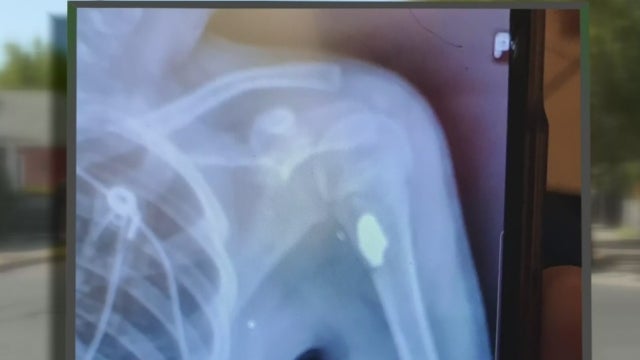

The whole time, a bullet was lodged in her arm. It was a bullet doctors could not remove for nearly a month due to medical complications.